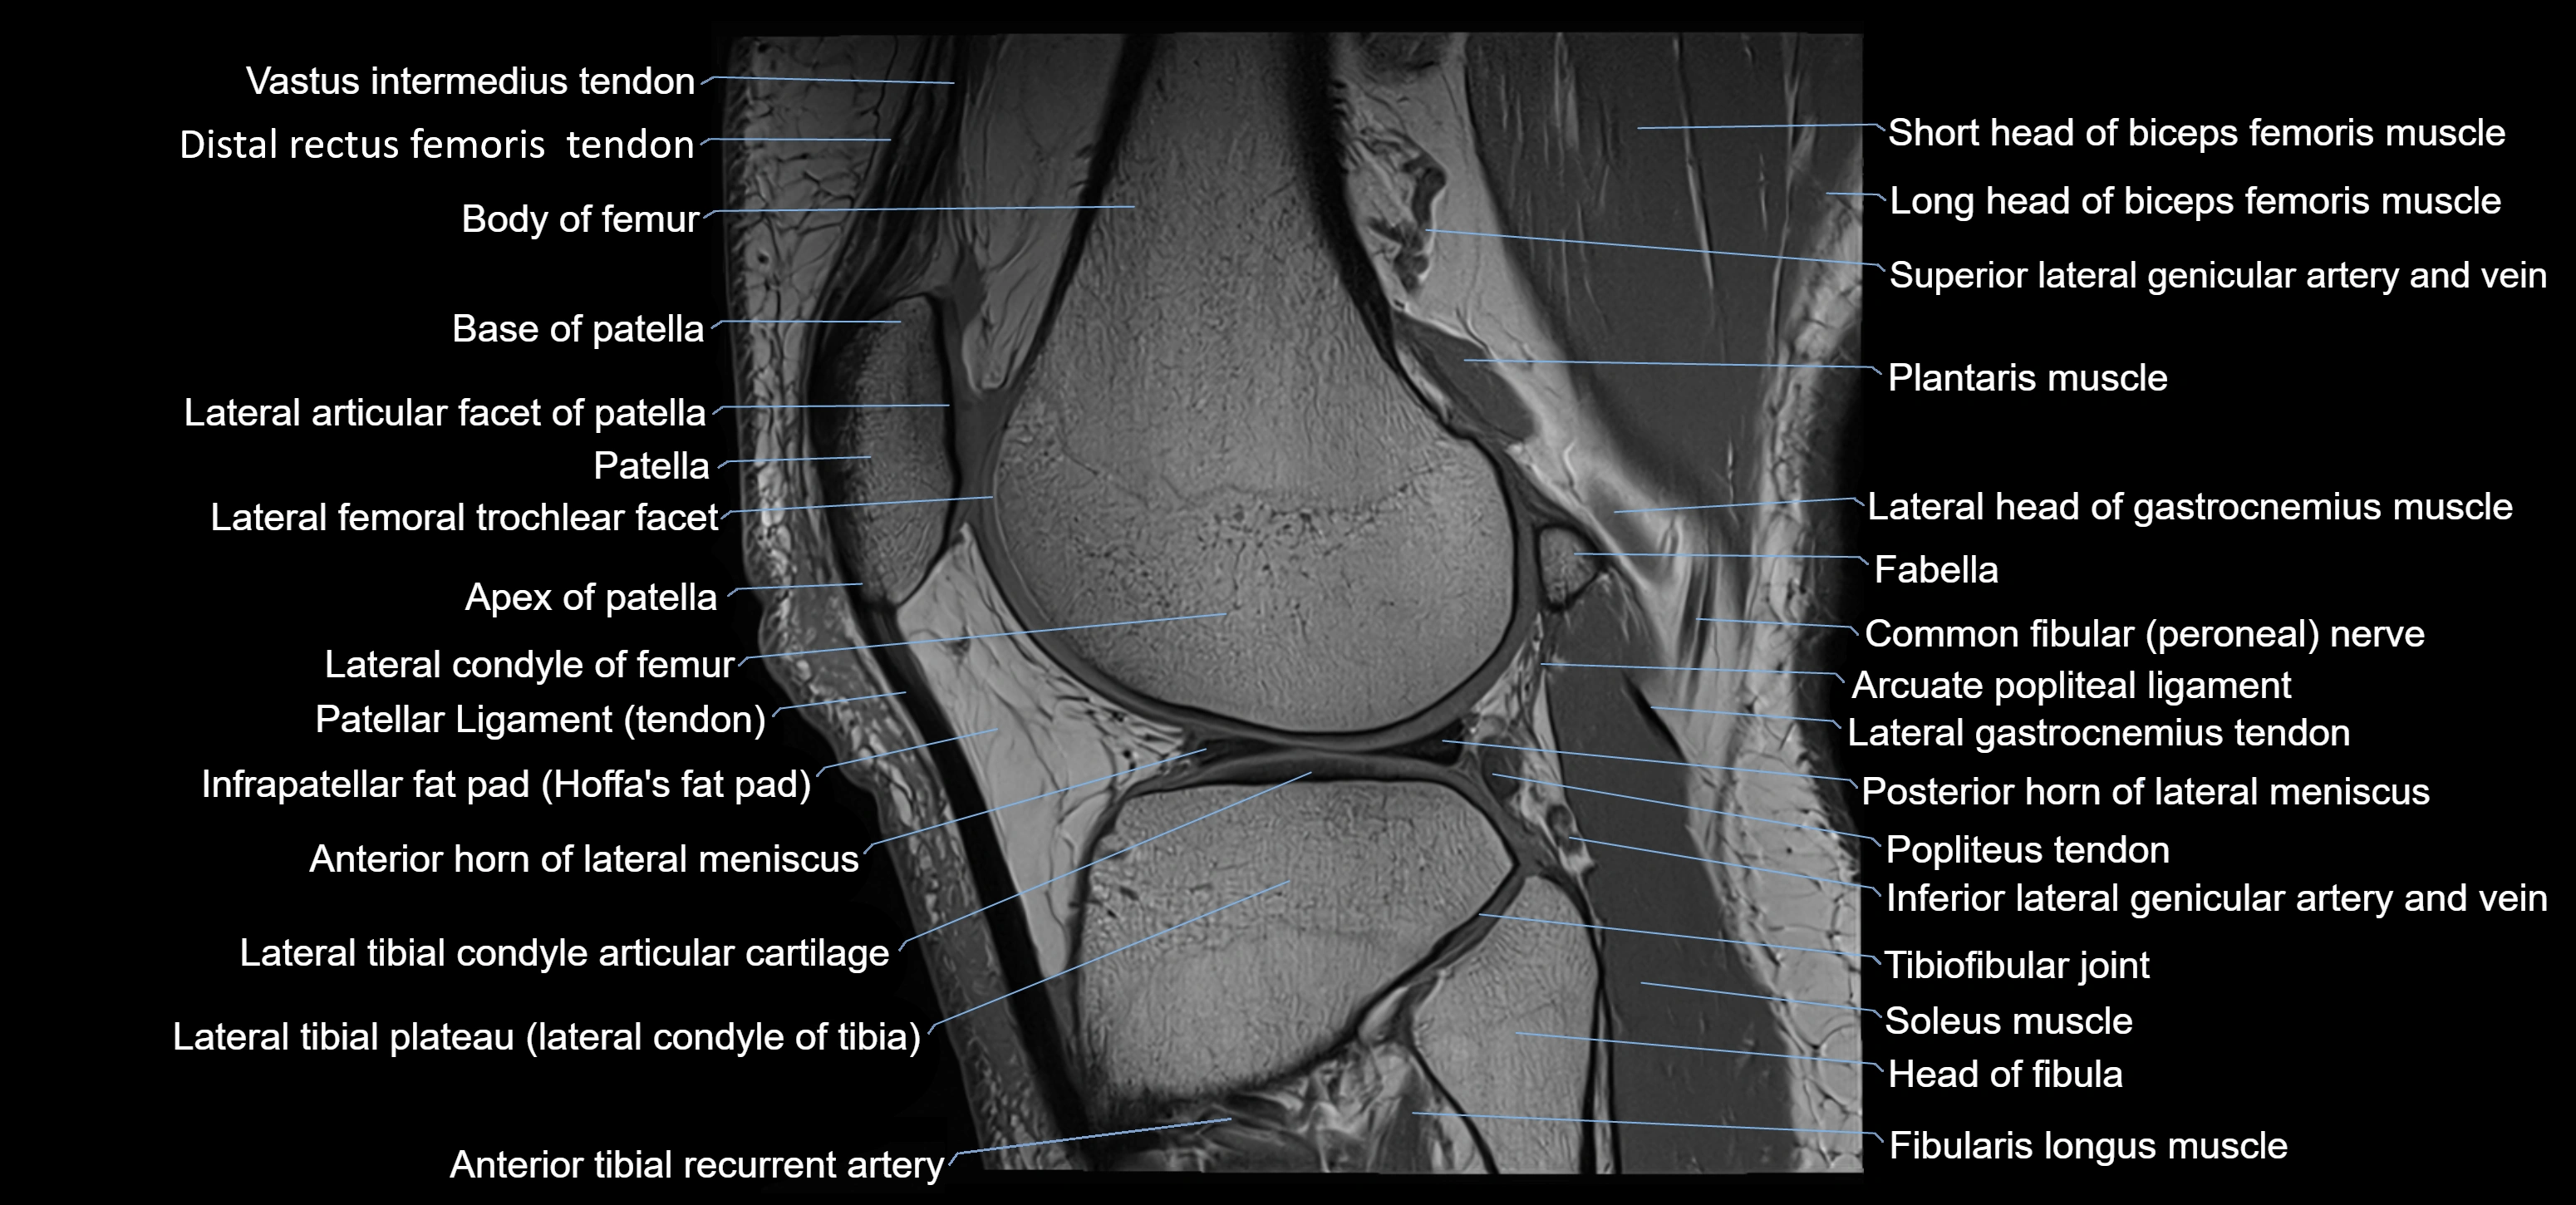

- Anterior horn of lateral meniscus

- Apex of patella

- Arcuate popliteal ligament

- Base of patella

- Body of femur

- Body of lateral meniscus

- Common fibular nerve

- Distal rectus femoris tendon

- Distal vastus intermedius tendon

- Fibularis longus muscle (peroneus longus muscle)

- Head of fibula

- Infrapatellar fat pad

- Lateral articular facet of patella

- Lateral condyle of femur

- Lateral gastrocnemius tendon

- Lateral head of gastrocnemius muscle

- Lateral intercondylar tubercle

- Lateral meniscus

- Lateral patellar retinaculum

- Lateral patellofemoral ligament

- Lateral tibial plateau

- Patellar tendon (patellar ligament)

- Plantaris muscle

- Popliteus tendon

- Posterior horn of lateral meniscus

- Soleus muscle

- Superior lateral genicular artery

- Superior lateral genicular vein

- Superior tibiofibular joint